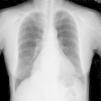

CaseA 65-year-old woman with an unremarkable medical history presented with intermittent dysphagia, which she reported had been causing a problem for approximately 1 year. The patient described a condition in which the passage of food took longer in the chest region, resulting in discomfort. Over time, the symptoms had worsened, and she had lost approximately 2kg in the previous 6 months. She finally sought medical attention in the outpatient department of our hospital. The initial physical examination findings were normal, except for an unexplained sinus tachycardia (an intermittent heartbeat of approximately 110 beats per minute). A subsequent esophagogram revealed a normal contour of the esophagus and the transit time was normal. Because the symptoms persisted and there was no sign of spontaneous regression, she underwent examination of the upper gastrointestinal tract by endoscopy. This did not provide any evidence of mucosal lesion, but the gastroenterologist did report an abnormal submucosal elevation in the lower third of the esophagus, approximately 2–3cm proximal to the esophagogastric junction (Fig. 1). Chest X-ray revealed a huge ovoid opacity in the right lower lung region adjacent to the mediastinum (Fig. 2). Computed tomographic scan indicated an enormous, low-density neoplasm in the posterior mediastinum, with a slight displacement of the esophagus (Fig. 3A), liver and inferior vena cava (Fig. 3B). Heart ultrasound revealed minimal right atrial and ventricular compression.

Chest radiograph showed one very large ovoid and well-demarcated opacity in right lower lung field. The silhouette sign is negative because the tumor margin can be differentiated from both the right heart border and diaphragm dome, indicating that the location of tumor is in the posterior mediastinum.